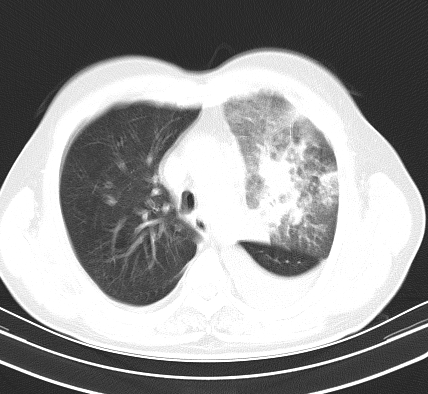

以下是引用老爱克斯新网客在2008-7-31 6:30:00的发言:[br]左肺上叶大片状病灶,左肺上叶支气管狭窄呈鼠尾状,左肺门增大,纵隔内见肿大淋巴结,左侧胸腔积液,余肺清晰。左肺中心型肺癌淋巴结转移,

以下是引用zjb在2008-7-31 6:32:00的发言:[br]左侧中心性肺癌 阻塞性肺炎 肺不张 胸腔积液 建议气管镜

以下是引用zjzjr在2008-7-31 8:45:00的发言:[br]考虑左侧中心性肺癌伴阻塞性肺炎,左肺上叶肺不张,纵隔淋巴结转移;左侧胸腔积液。建议行纤支镜检查。

以下是引用sdzyy在2008-7-31 8:47:00的发言:[br]病灶较治疗前有所进展,胸水增多, 左侧中心性肺癌 并 阻塞性肺炎 肺不张 胸腔积液 可能性大; 建议气管镜检查。 [br] [br]